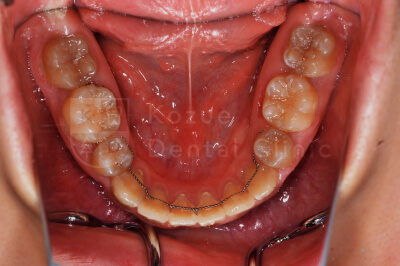

CASE PHOTOcase2:上下顎前突・正中離開

症例:上下顎前突・正中離開

口元の突出、口が閉じずらいことを気にして来院、マルチブラケット装置にて治療しました。